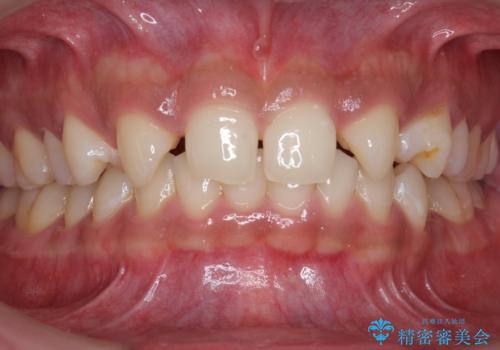

前歯のすきま 生まれつき歯が少ないのを治療

- 前歯の隙間を気にして来院。

生まれつき上の歯が二本少ない状態でした。

バラバラに位置している前歯の位置を矯正治療で修正してからブリッジを装着しています。

また、全体矯正もご希望でしたので下の歯のがたつきや、すれ違っているかみ合わせも治療しています。